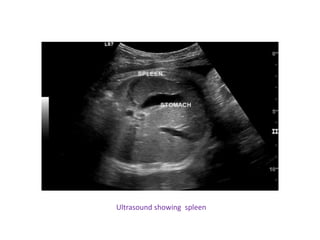

• Ultrasound-sensitive and non invasive

Ultrasound showing spleen